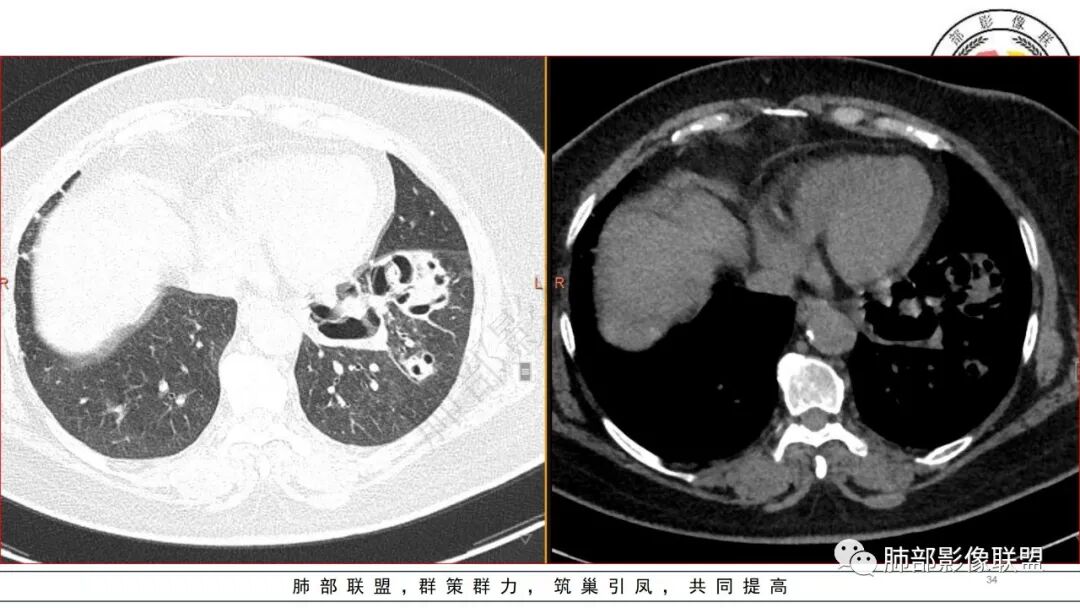

老年患者,糖尿病病史14年,不规律降糖治疗,血糖控制不佳,咳嗽、喘息两天就诊,查血常规白细胞轻度升高,CRP显著升高,首诊CT提示左下基底大片实变,边界不清,周围播散灶,短期复查病灶呈吸收好转趋势,并出现多发空洞,空洞形态不规则,病灶内未见气液平,考虑感染性病变:

2.左肺下叶大范围实性密度影,散乱,边界不清,可见液化空洞,病变肺体积轻度增大。支气管相关(相应支气管闭塞)。

3.五天后及十三天后病灶变化明显,实性密度影吸收缩小,边界趋于清楚,显示多空腔。

4.双侧胸腔未见积液。

5.扫描范围内未见肝脏密度异常影。

1.局限于单肺叶的大范围实性密度影,边界不清,看不出外壁的液化空洞,多符合化脓性感染。